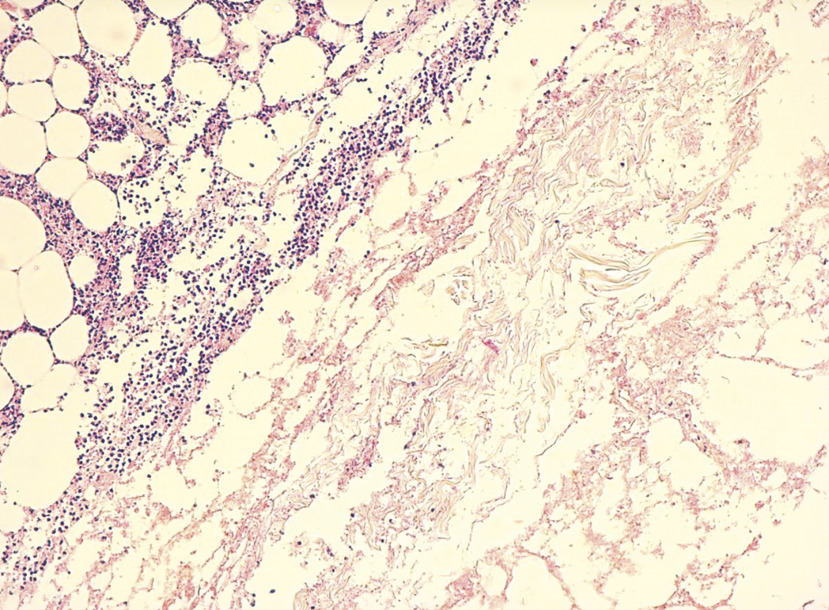

Cet homme de 58 ans consultait pour de multiples lésions nodulaires noirâtres, apparues depuis quelques mois sur une lésion nodulaire post-traumatique évoluant depuis 1 an sur la face interne de la jambe gauche ; ces lésions dont quelques-unes avaient une surface ulcérée étaient étagées le long du membre (fig. 1 ). Ces lésions étaient entourées d’un placard achromique bien limité, rappelant l’aspect d’un vitiligo (fig. 2 ) ; le patient ne rapportait pas d’antécédent personnel ou familial de vitiligo. Une biopsie de la lésion initiale confirmait le diagnostic de mélanome avec un indice de Breslow à 9 mm (fig. 3 ). Le bilan d’extension montrait de multiples nodules pulmonaires et des adénopathies d’allures tumorales au niveau inguinal et iliaque interne et externe gauche. Ce patient décédait 1 mois plus tard.